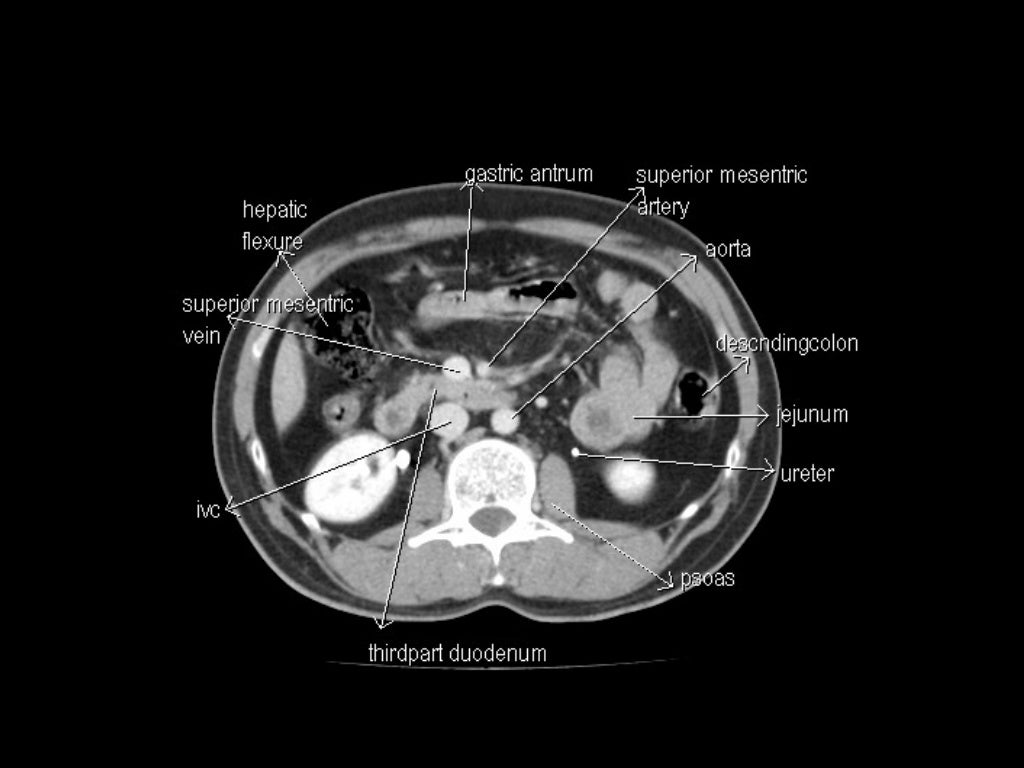

Abdomen human man CT scan 12872427 Stock Photo at Vecteezy Biology Diagrams The data sets were designed to serve as (1) a reference for the study of human anatomy, (2) public-domain data for testing medical imaging algorithms, and (3) a test bed and model for the construction of network-accessible image libraries. The CT data consist of axial CT scans of the entire body taken at 1mm intervals at a pixel resolution Computed tomography (CT) scanning is an extremely common imaging modality in modern medicine.With advancements in technology, it is rapidly replacing many diagnostic radiographic procedures. In this article, we will outline the basic science behind CT scans, describe the principles of interpretation, and highlight their advantages and drawbacks compared to other imaging techniques. CT Scan Anatomy Overview. CT scans, or Computed Tomography scans, are essential tools in modern medicine. They provide detailed images of the inside of your body and are particularly useful for diagnosing conditions that affect the bone and soft tissues. Understanding CT scan anatomy is crucial for interpreting these images accurately.